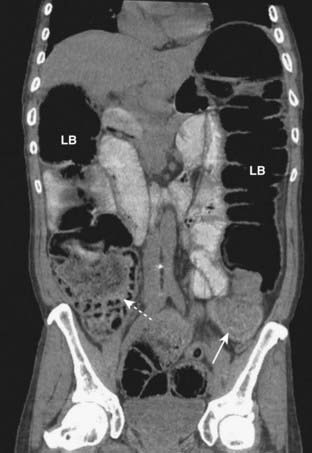

image

Figure 14-15 Large bowel obstruction from carcinoma of the colon.

This coronal reformatted CT scan of the abdomen and pelvis shows dilated cecum (dotted white arrow) and large bowel (LB) to the level of the distal descending colon where a large soft tissue mass is identified (solid white arrow). This mass was surgically removed and was an adenocarcinoma of the colon.